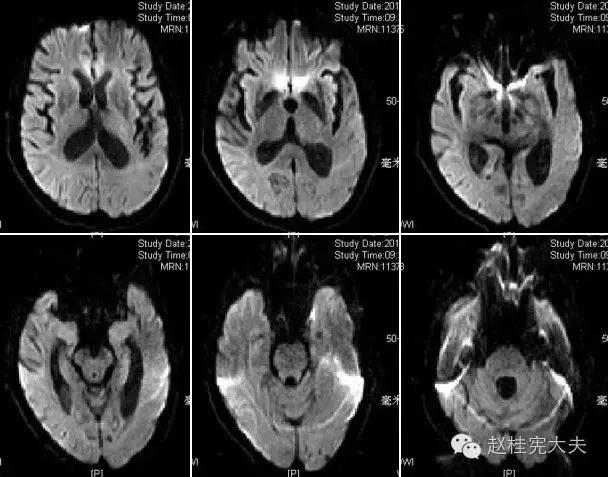

完善检查,头颅MRI回报:左侧颞顶枕叶急性梗死灶。

当看到磁共振片子的时候,我知道,我们忽略了一些东西......

患者的磁共振影像不符合脑血管病的血供分布,跨了大脑中动脉和大脑后动脉范围,且病灶偏皮层分布。大脑前、中、后动脉血供分布(横断面)见下图

这不是一个真的“脑卒中”,而是一个“卒中样发作”。

上周,于发病后2月复查磁共振:

到此为止,MELAS的诊断应该在没有基因确诊的情况下在临床上得到认可了,患者明确诊断为线粒体脑肌病伴乳酸血症和卒中样发作(MELAS),解释了患者的所有症状,患者母亲不明原因地死亡也得以真相大白,患者的相关亲属们在未来的人生路上也多了一份呵护......